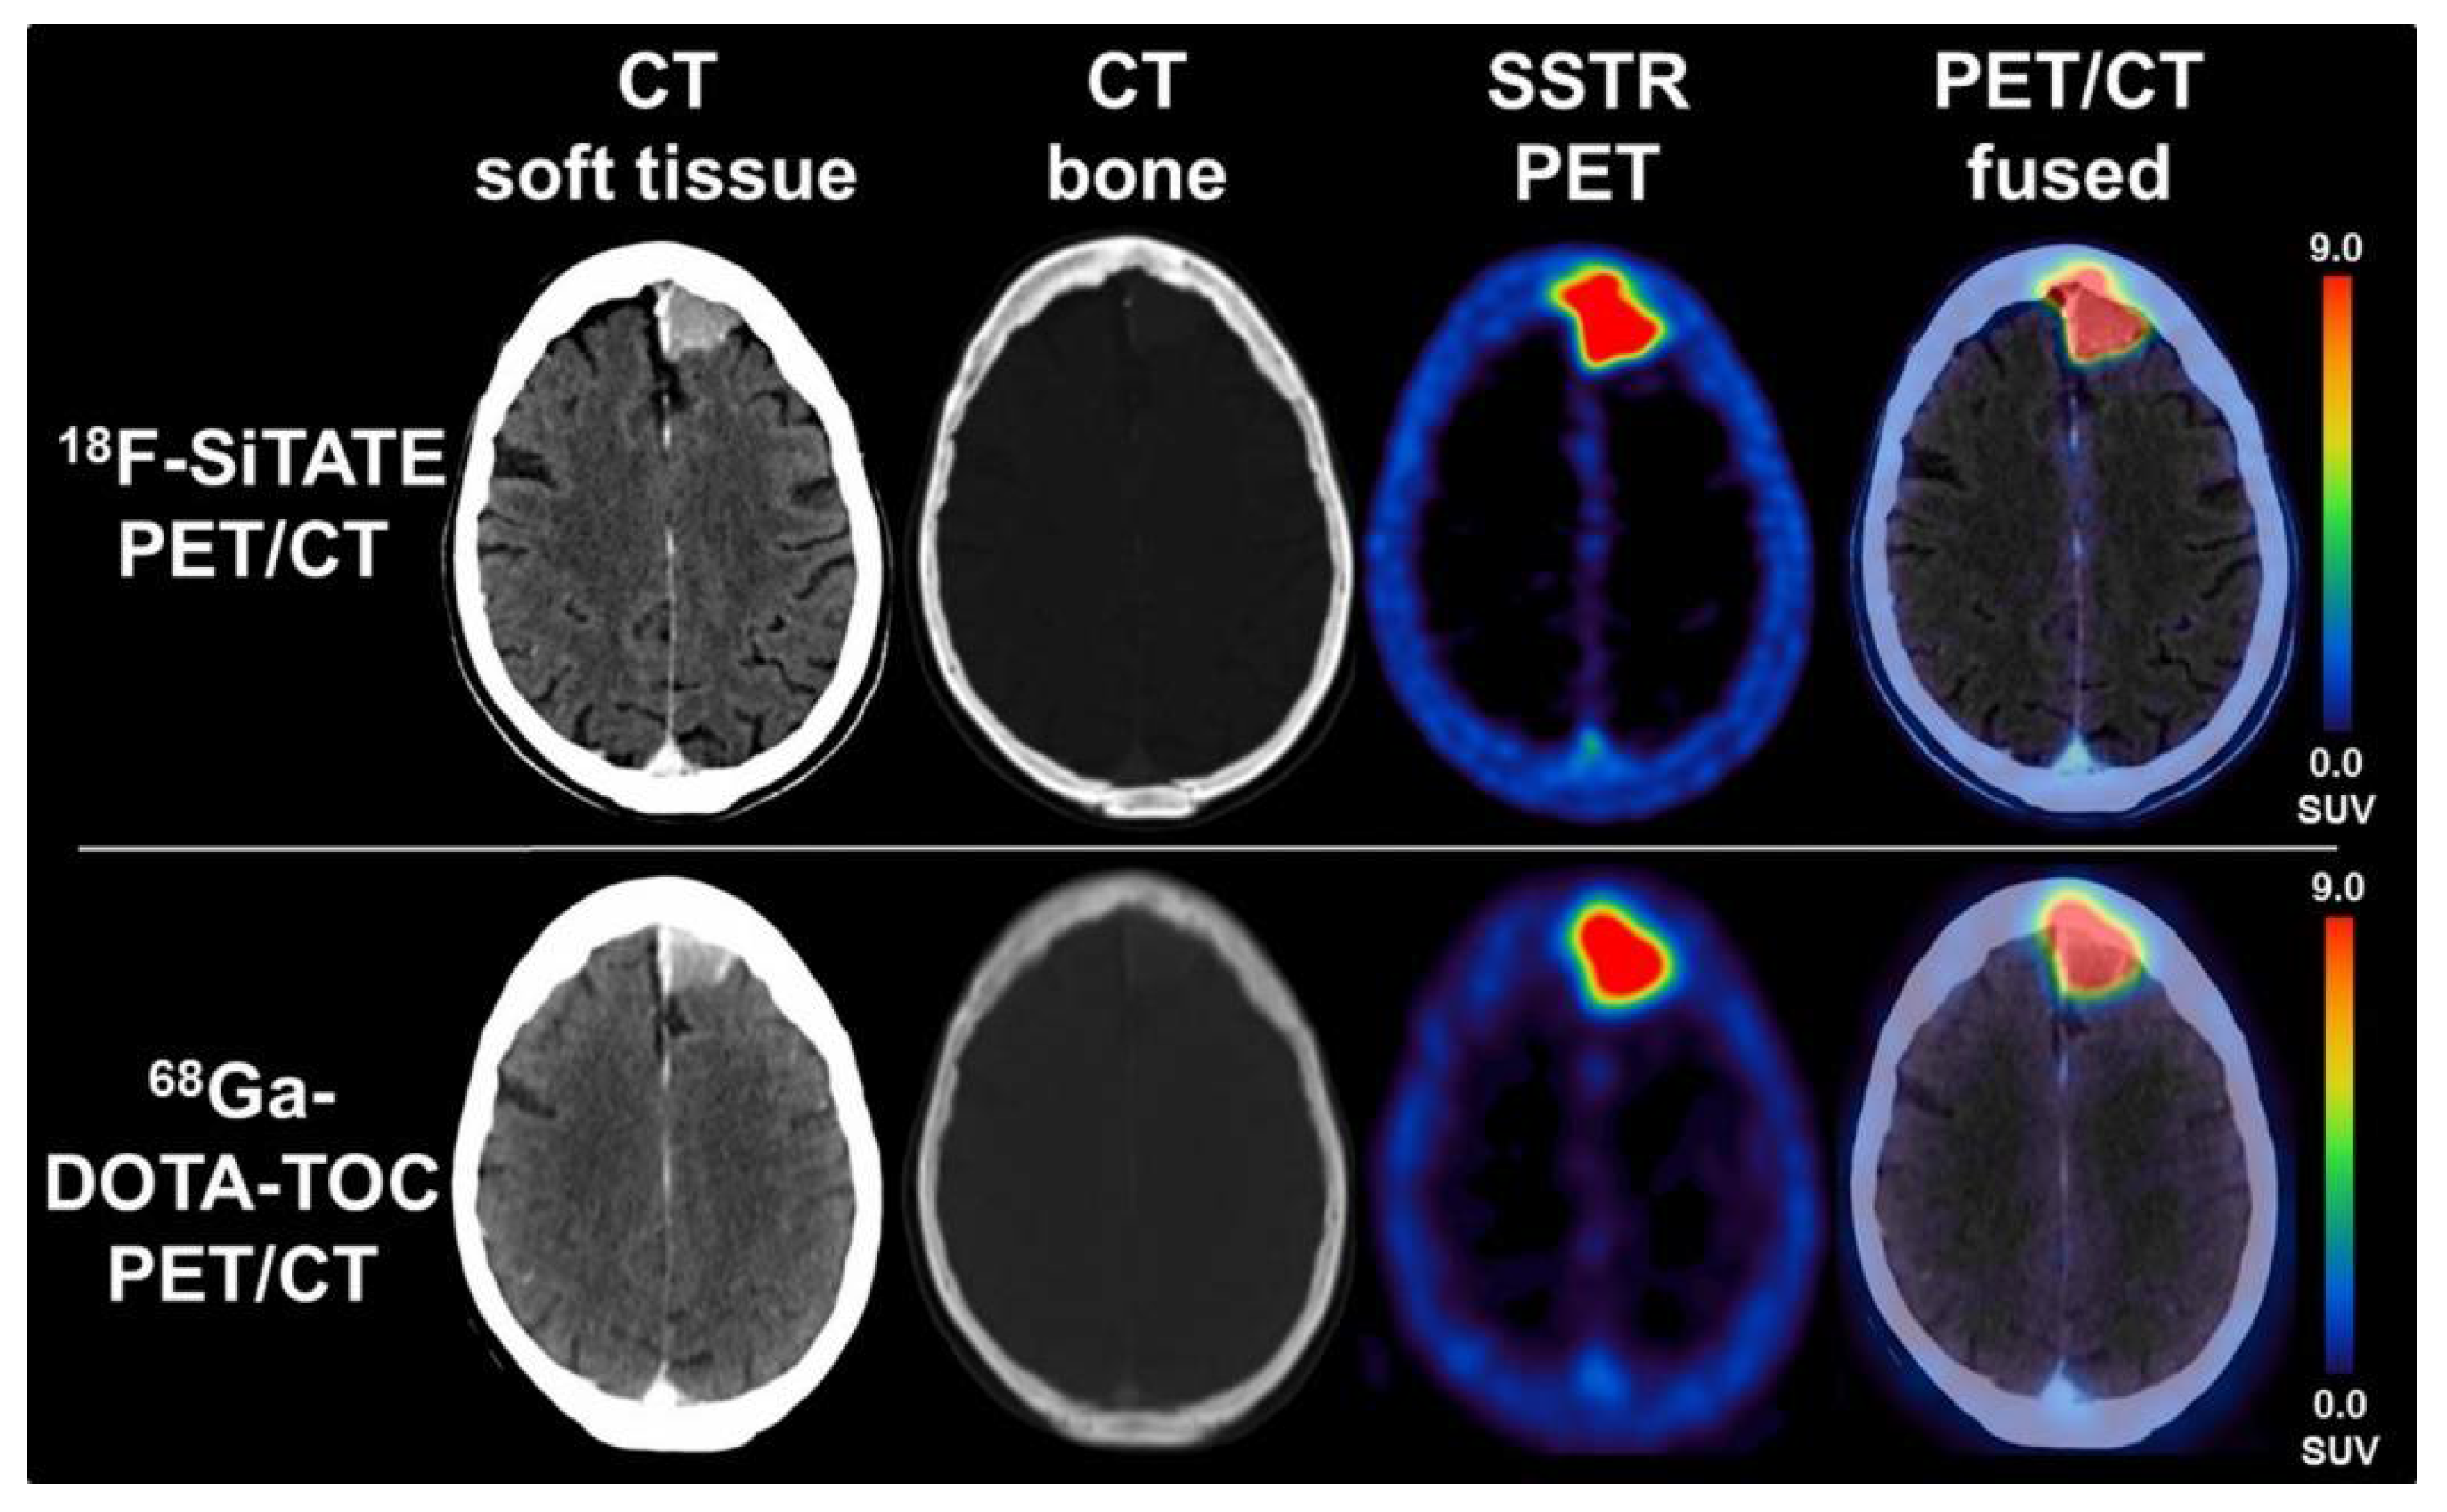

- Unterrainer, M.; Lindner, S.; Beyer, L.; Gildehaus, F.J.; Todica, A.; Mittlmeier, L.M.; Jurkschat, K.; Wängler, C.; Wängler, B.; Schirrmacher, R.; et al. PET Imaging of Meningioma Using the Novel SSTR-Targeting Peptide 18F-SiTATE. Clin. Nucl. Med. 2021, 46, 667–668. [Google Scholar] [CrossRef]

- Niedermoser, S.; Chin, J.; Carmen, W.; Kostikov, A.; Bernard-gauthier, V.; Vogler, N.; Soucy, J.; Mcewan, A.J.; Schirrmacher, R. In Vivo Evaluation of 18F-SiFAlin-Modified TATE: A Potential Challenge for 68Ga-DOTATATE, the Clinical Gold Standard for Somatostatin Receptor Imaging with PET. J. Nuc. Med. 2015, 56, 1100–1105. [Google Scholar] [CrossRef]

- Ilhan, H.; Lindner, S.; Todica, A.; Cyran, C.C.; Tiling, R.; Auernhammer, C.J.; Spitzweg, C.; Boeck, S.; Unterrainer, M.; Gildehaus, F.J.; et al. Biodistribution and first clinical results of 18 F-SiFAlin-TATE PET: A novel 18 F-labeled somatostatin analog for imaging of neuroendocrine tumors. Eur. J. Nucl. Med. Mol. Imaging 2020, 47, 870–880. [Google Scholar] [CrossRef]